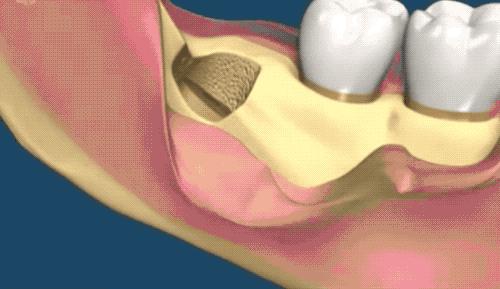

露出牙槽骨后,先削除一部分骨头,露出躺卧如睡美人的横阻生智齿...如果是已经出肉的智齿,就没这一步了。

也是先切开牙肉,翻开并露出骨头,切下牙冠后取出,再处理下面的牙根。

3.1 减少损伤 在神经束与根尖非常接近,易发生下牙槽神经损伤,此时所采用的外科技术(如牙齿劈开)必须尽量减少神经束被切断、牵拉、撕裂或者挤压,以避免神经损伤的危险。